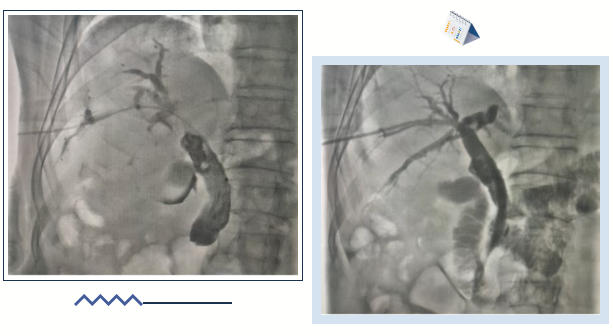

近日,在白利君主任团队的精准操作下,北京大学第三医院秦皇岛医院肿瘤科为一位因胆管恶性肿瘤引发胆道梗阻、胆红素大幅升高的老年患者成功施行PTCD(经皮经肝胆管穿刺引流术)+胆道支架置入术。术后,患者胆红素水平迅速降低,肝功能显著改善,临床症状得到明显缓解,充分彰显了医院在肿瘤并发症微创救治领域的技术能力与救治效能,为胆道梗阻患者提供了可靠的治疗支撑。

75岁的张大爷近两日因食欲明显下降、全身乏力,并出现皮肤黏膜及眼结膜显著黄染,伴尿色加深、全身瘙痒等症状前来就医。检查结果显示,其血清总胆红素水平显著升高,肝功能指标异常,影像学检查进一步提示胆管因肿瘤压迫而发生梗阻。为迅速解除胆道梗阻、改善肝功能,并为后续抗肿瘤治疗创造有利条件,白利君主任团队果断决定为患者施行经皮肝穿刺胆道引流术(PTCD)联合胆道支架置入术。

PTCD是一种在超声或X线引导下进行的微创介入技术,通过皮肤穿刺直达肝脏内扩张的胆管,从而建立有效的胆汁引流通道。术中,医疗团队在局部麻醉下,借助影像设备实现精准定位,经皮肤仅一个针眼大小的穿刺点,成功穿刺扩张的胆管并置入引流管,使原本淤滞堵塞的胆汁得以顺利通过引流管排出体外,或通过支架重建胆道内引流通路,有效缓解梗阻症状。